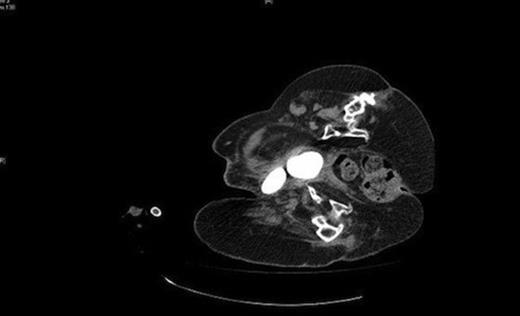

CT demonstrating the two bladder calculi pointing towards the right groin

Vesicolithotomy was performed removing the calculi by enlarging the fistulous opening. (Fig 3) Two calculi measuring 40mm × 43mm × 30mm and 43mm × 50mm × 33mm were extracted. (Fig. 4) The suprapubic catheter was changed and the fistula was left open and urine leakage continued to decrease in quantity until the fistula tract closed.